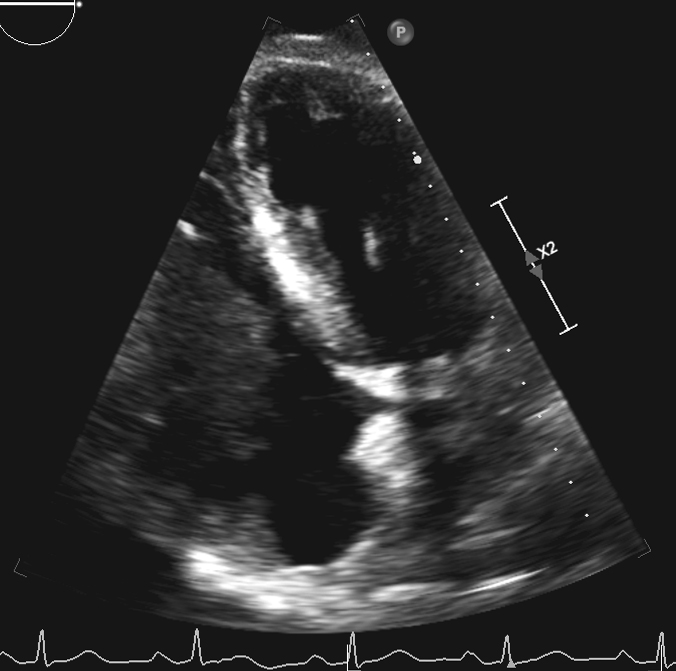

In the operating room, the patient underwent general endotracheal anesthesia. After his sternum had been divided, his right atrium and ventricle appeared distended, and there was evidence of moderate right ventricle dysfunction. On palpation of the right atrium and ventricle, the mass could be easily felt. After Heparin administration, the aorta was cannulated and there was bicaval venous cannulation. The heart was arrested and a right atriotomy was performed. The mass was stuck to the right atrium (Figure 2A and Figure 2B), tricuspid valve, and right ventricle. There was also invasion into the myocardium of the right ventricle. There was no possibility of excision of the mass in its entirety, but multiple biopsies were sent for evaluation (Figure 3). The frozen section returned as lymphoma.